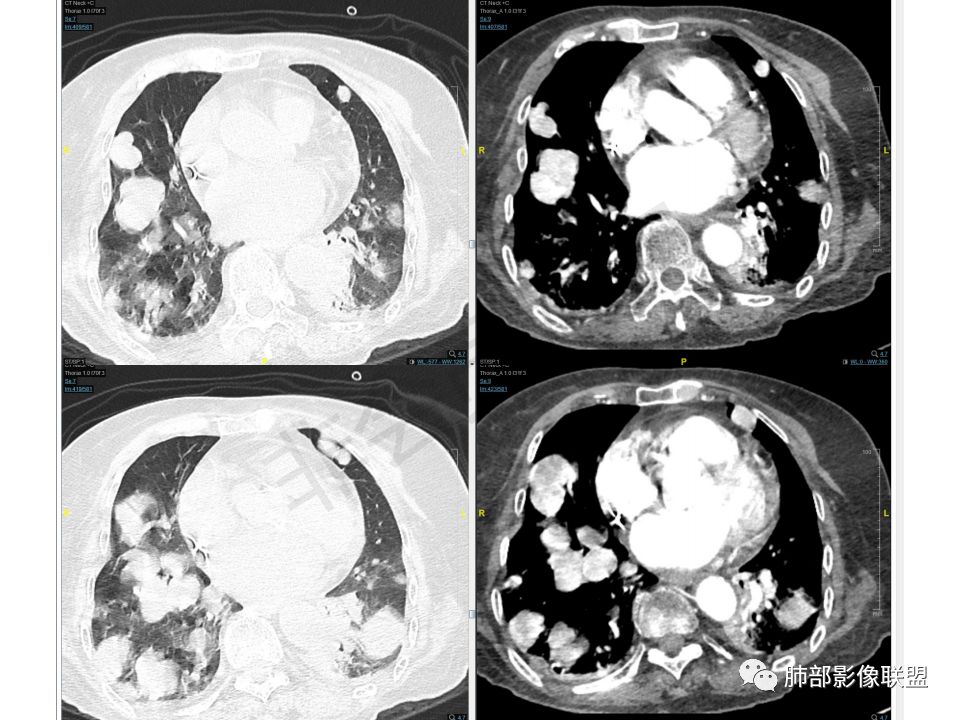

老年女性,两肺多发球形结节,边缘光滑,部分位于胸膜下,纵隔淋巴结肿大不明显,胸水少量,增强后强化明显,考虑转移,肉瘤转移的可能,补充下病史。气管内新生物,是不是二元,息肉或肿瘤

老年女性,间断咯血两年。影像:气管内带蒂结节,边缘光滑明显强化。左肺下叶背段支气管截断,远端不张。两肺散在大小不等结节及磨玻璃影,明显强化,磨玻璃影考虑合并出血可能。纵隔多发淋巴结肿大,两侧支气管受压。综合考虑:肺癌伴两肺转移。原发气管结节还是左肺下叶背段?腺样囊性癌?类癌?

老年女性,慢性病程。两肺多发类圆形结节、肿块,边缘光滑,胸膜下分布为主,显著强化,考虑转移瘤。气管内肿块,边缘光整,强化方式与肺内肿块一致,一元考虑气管肉瘤并双肺转移。

双肺多发大小不等结块,边缘光滑,随机分布,部分融合,密度不均匀,增强后可见不均匀明显强化(富血供),肺门及纵隔淋巴结肿大融合,老年女性,综合考虑转移瘤,建议查全身脏器,必要时Pet-CT, 鉴别小细胞肺癌。

之前碰见过一例肾透明的肺内转移,强化也是很明显,几年的随访也没有变化。强化这么明显的多发病灶,没有增粗的供血和引流血管,不考虑AVM。如果先天发育所致,还想到的就是毛细血管扩张症,强化程度达不到,病变位置也不对。病灶随机分布,大小不等,考虑血播,首先考虑到的是转移瘤,倾向于气管原发,类癌?

晨读:老年女性,间断咯血2年,呼吸困难2月,加重3天,高血压冠心病史40余年,阵发性房颤20余年,老年痴呆10年,贫血5年,气管腔内不规则结节,强化明显,双肺多发圆形或类圆形结节,强化明显。临床症状病史加影像改变综合分析,有三种可能:1、气管原发恶性肿瘤伴肺内转移,2、气管与肺部均为富血供转移,原发待定,3、气管内良性肿瘤性结节,肺内恶性转移。个人倾向于气管类癌或非典型类癌合并肺上转移,并类癌综合征可能,其他两个可能待鉴别,建议查甲状腺,腹部CT,肿瘤标志物。